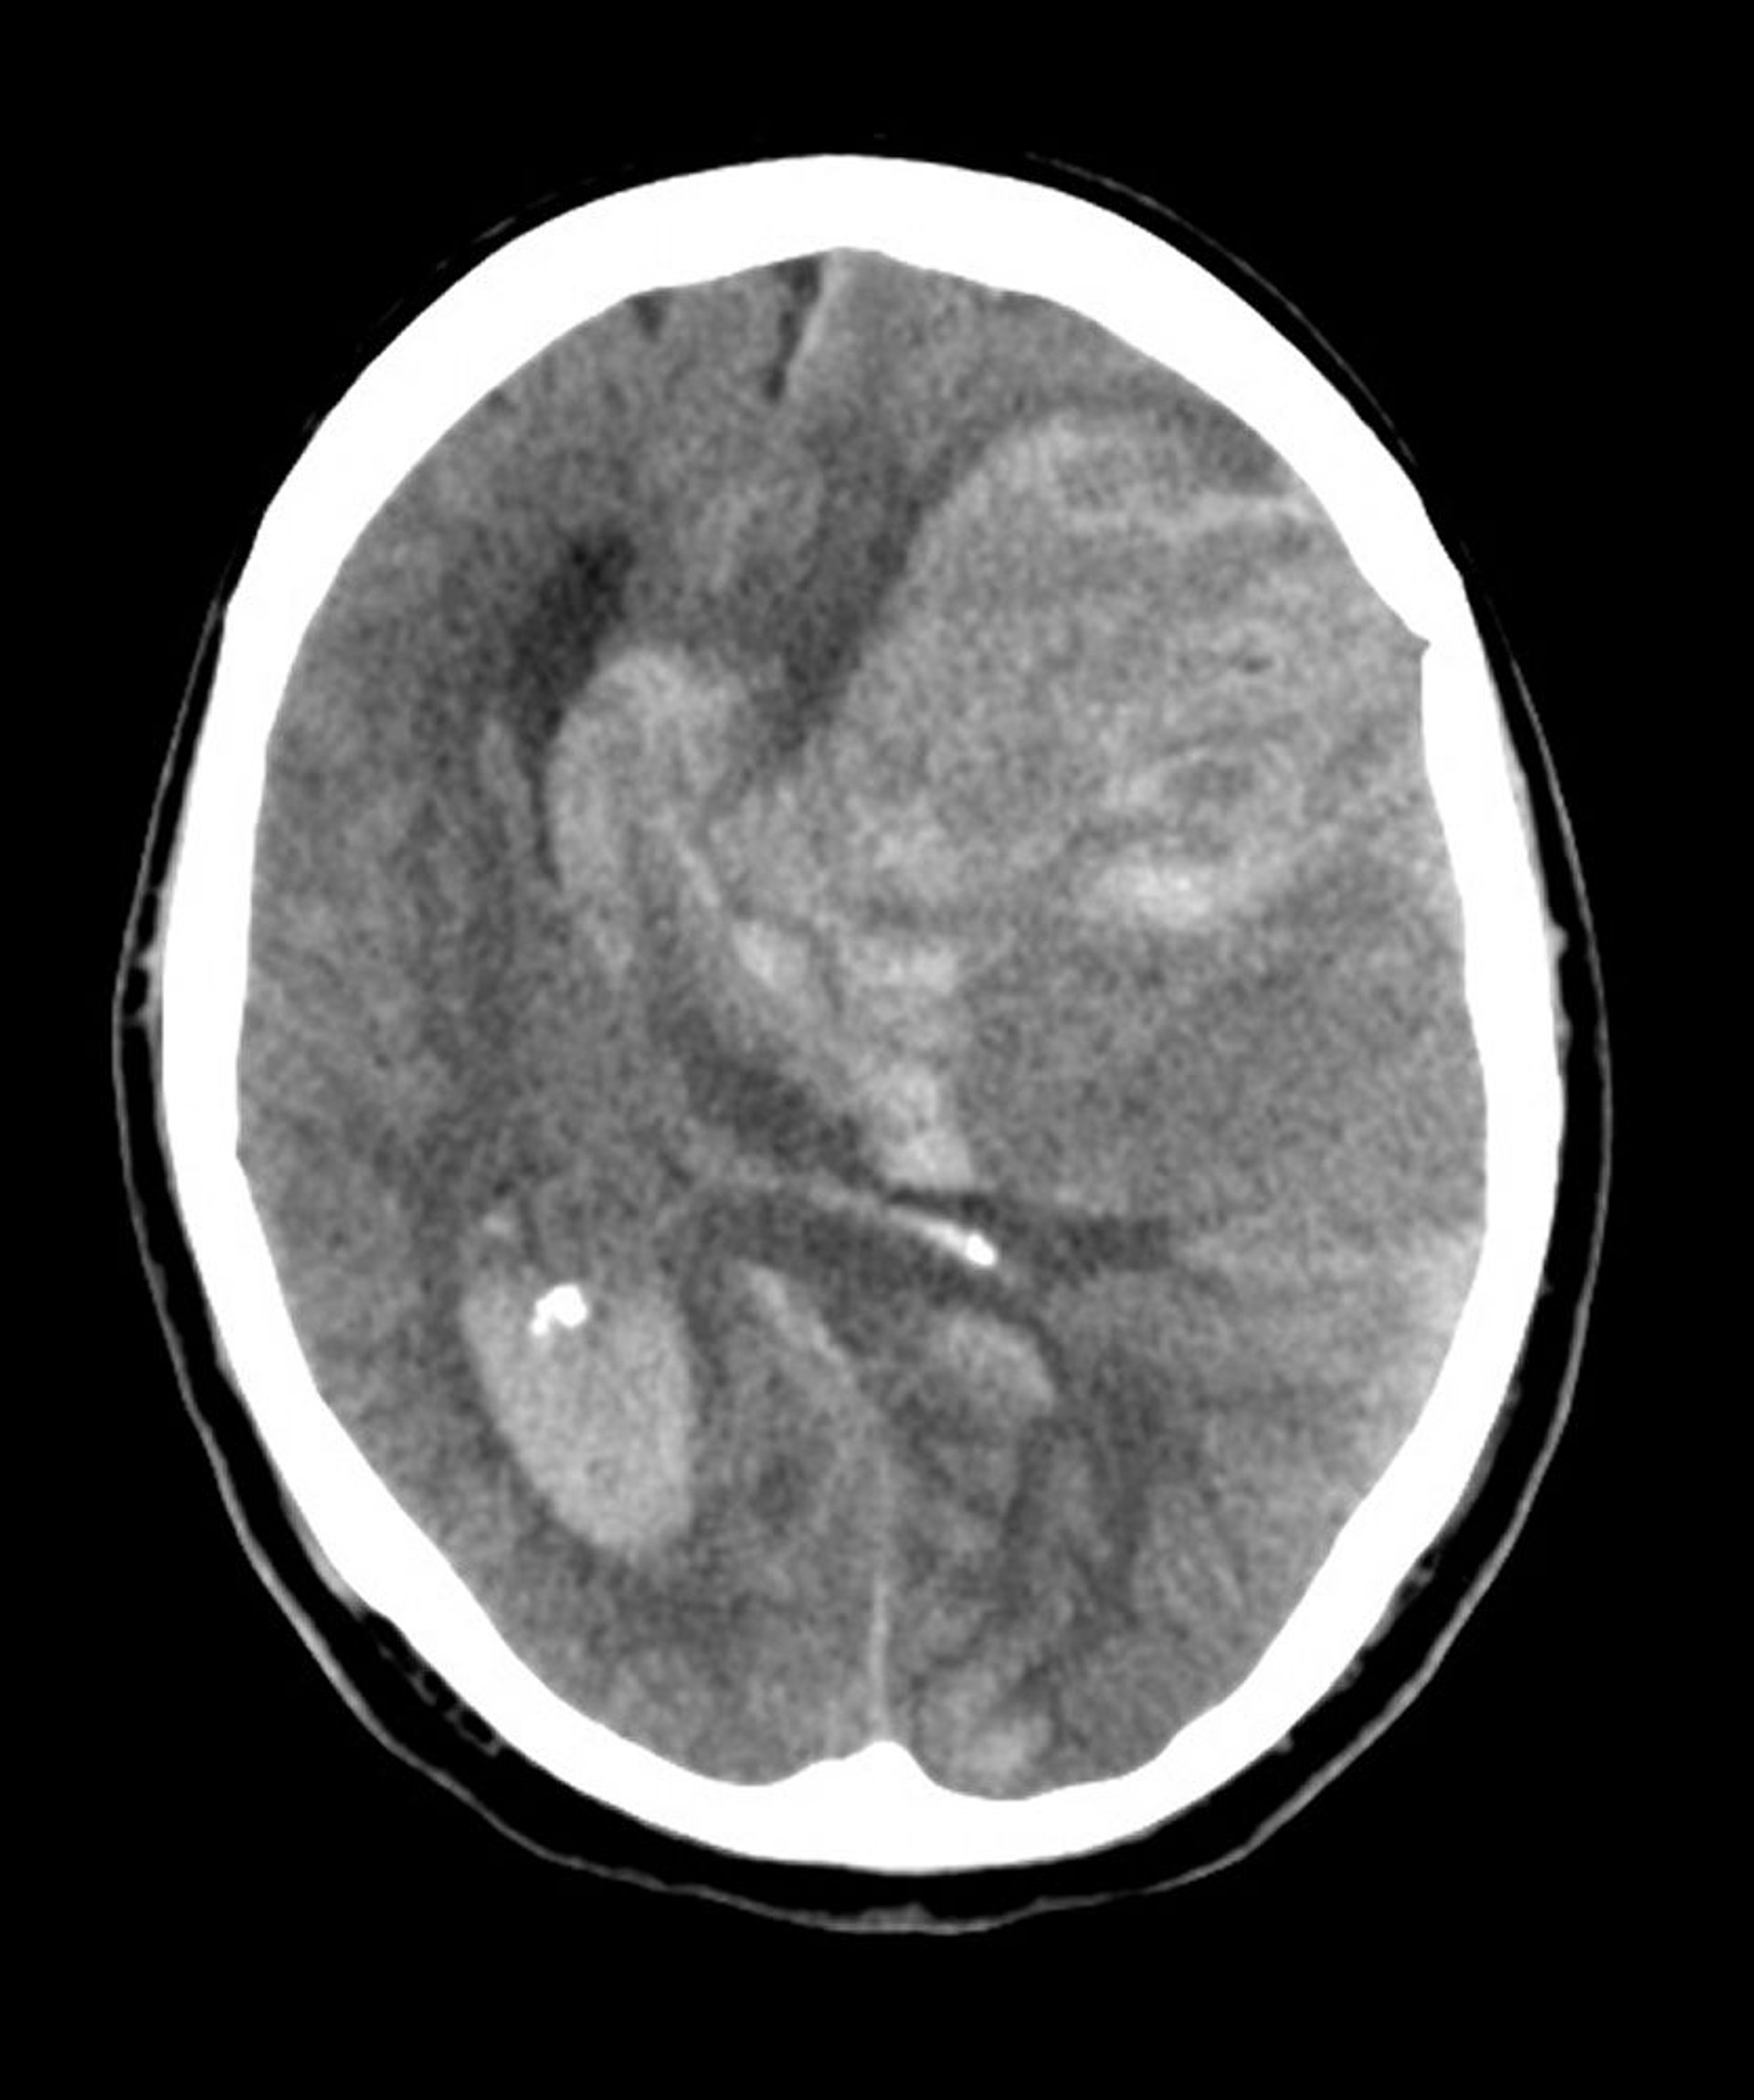

Ernia subfalcina

L'erniazione subfalcina è il tipo più comune di erniazione cerebrale. In questa immagine, il cervello sinistro è erniato sotto il bordo libero della falce cerebrale (freccia) poiché l'emorragia a seguito di un infarto nell'arteria cerebrale media ha aumentato la pressione intracerebrale.